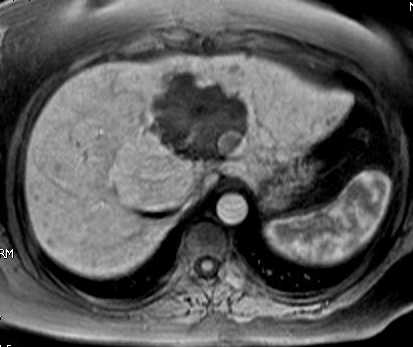

Imagerie T1 avec injection de Multihance 25 s, 1 mn, 2 mn.

Les angiomes ont un comportement habituel Hypo T1 se renforçant de façon très progréssive et intense (même densité que les vaisseaux). présence de nodules iso T1 franchement hypervasculaires au temps artériel et devenant isointense au temps portal.